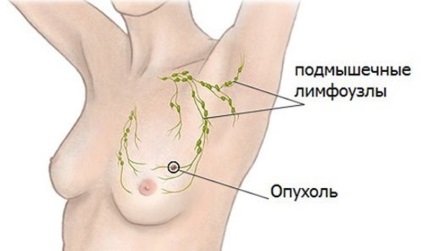

Fibroadenomatosis de san este cel mai frecvent observate sub forma unor tumori individuale. Mult mai puțin frecvente forme de boli multiple care afecteaza ambii sani. Tumorile de sân dreapta și din stânga nu sunt diferite unul de altul. Unele femei cred că înfrângerea de san lasat mai periculoase din cauza amplasării aproape a inimii. Cu toate acestea, această versiune a confirmării oficiale nu este primit.

Fibroadenomatosis glandele mamare pot avea previziuni diferite. In unele cazuri, tumora creste rapid la o anumită dimensiune, atunci dezvoltarea sa este suspendată. Orice disconfort o femeie nu se simte. În timpul formării fibroadenoma mamare activă apar frunzelor imature. Tumora poate ajunge la 10 cm în diametru și ocupă mai mult de jumătate din piept. Datorită prezenței tumorilor mamare mari formă poate varia. In timpul sarcinii, dezvoltarea caracterului de fibroadenom devine previzibil. Acest lucru se datorează influenței hormonilor asupra țesutului glandular în care acestea cresc și să se pregătească pentru producția de lapte.